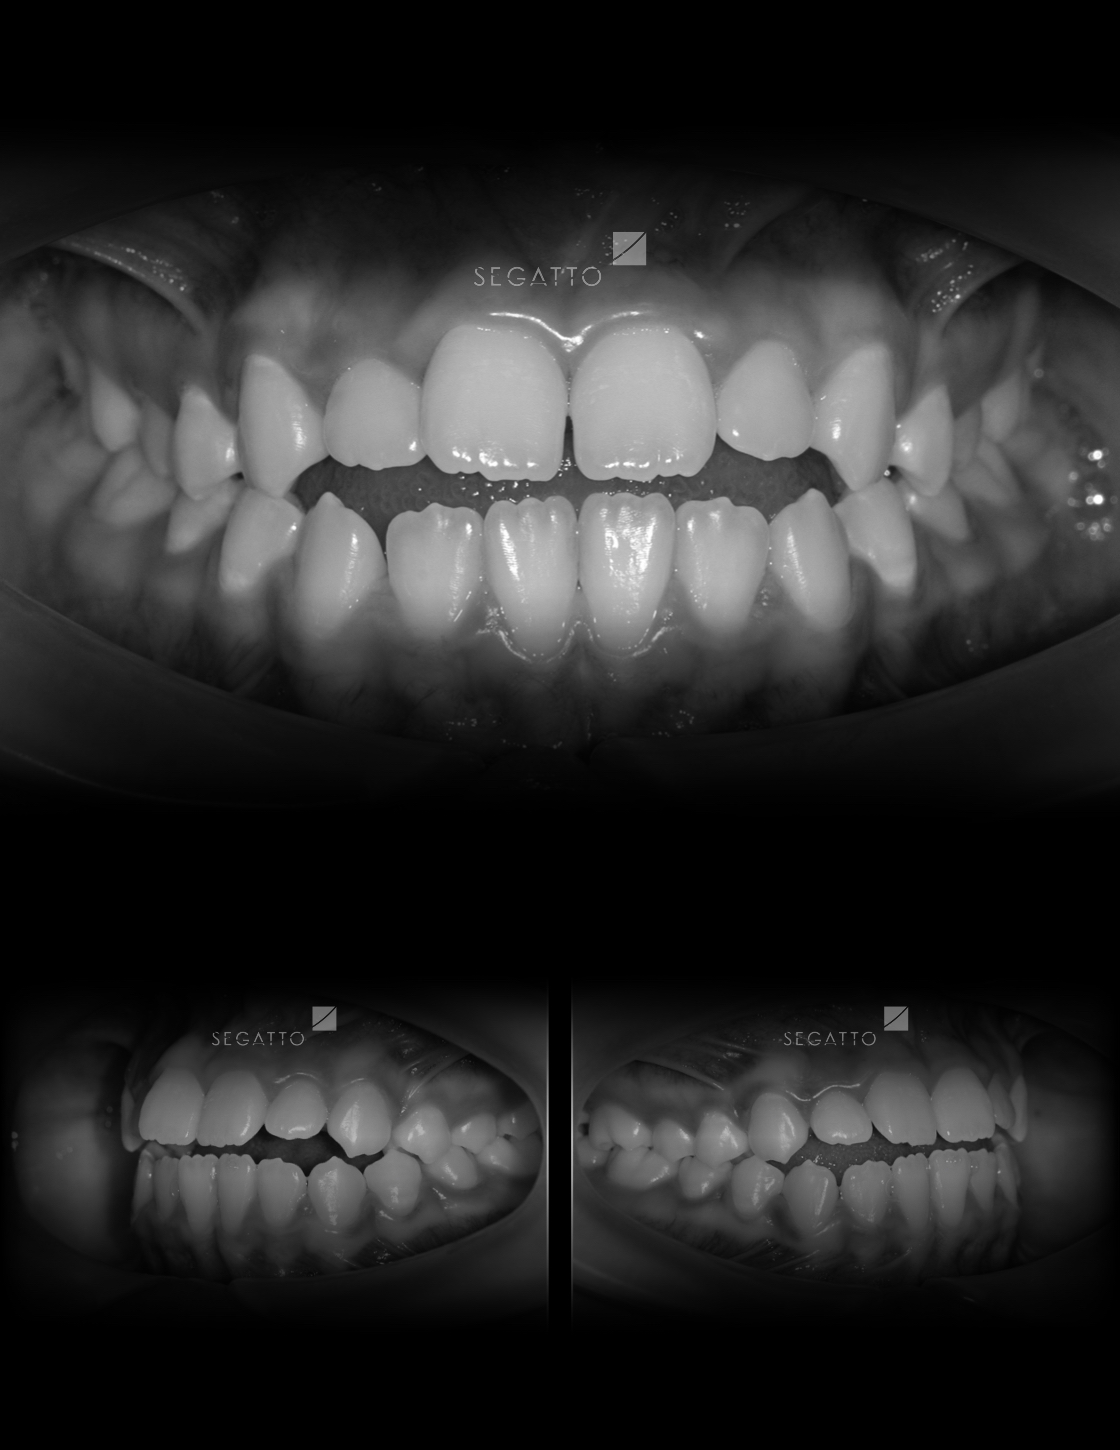

Orthodontics

Cases